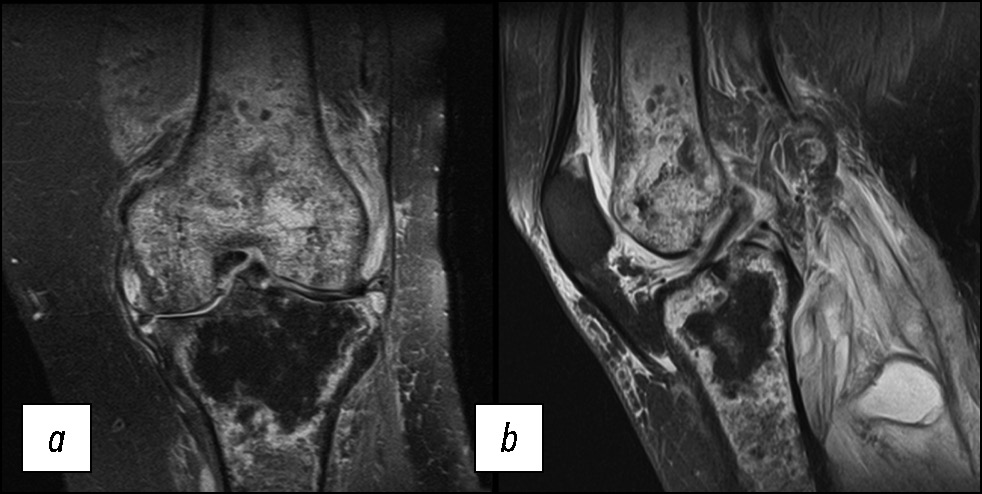

Особенностью отёка костной ткани, выявленного на МР-томограммах (рис. 8), является его локализация. Очаги встречаются как в нагружаемых (мыщелки бедренной и большеберцовой кости), так и в ненагружаемых областях (межмыщелковое возвышение). Нет чёткого отграничения здоровой кости от поражённых участков, что является отличием от вторичного остеонекроза костей, развивающегося, например, на фоне приёма глюкокортикостероидов. В то же время локализация в разных участках бедренной и большеберцовой кости подчёркивает вторичный характер поражения. Структура гиалинового хряща истончена равномерно, и его изменения не зависят от локализации отёка в костной ткани, что отличает отёк при ревматоидном артрите от остеита при деформирующем остеоартрите коленного сустава.

Рис. 8. МР-томограммы коленного сустава: a, b — корональная и сагиттальная проекции в режиме PD FS с подавлением сигнала от жировой ткани при ревматоидном артрите.

Fig. 8. MRI scans of the knee: a, b — coronal and sagittal views in to suppress the signal from adipose tissue with a rheumatoid arthritis.